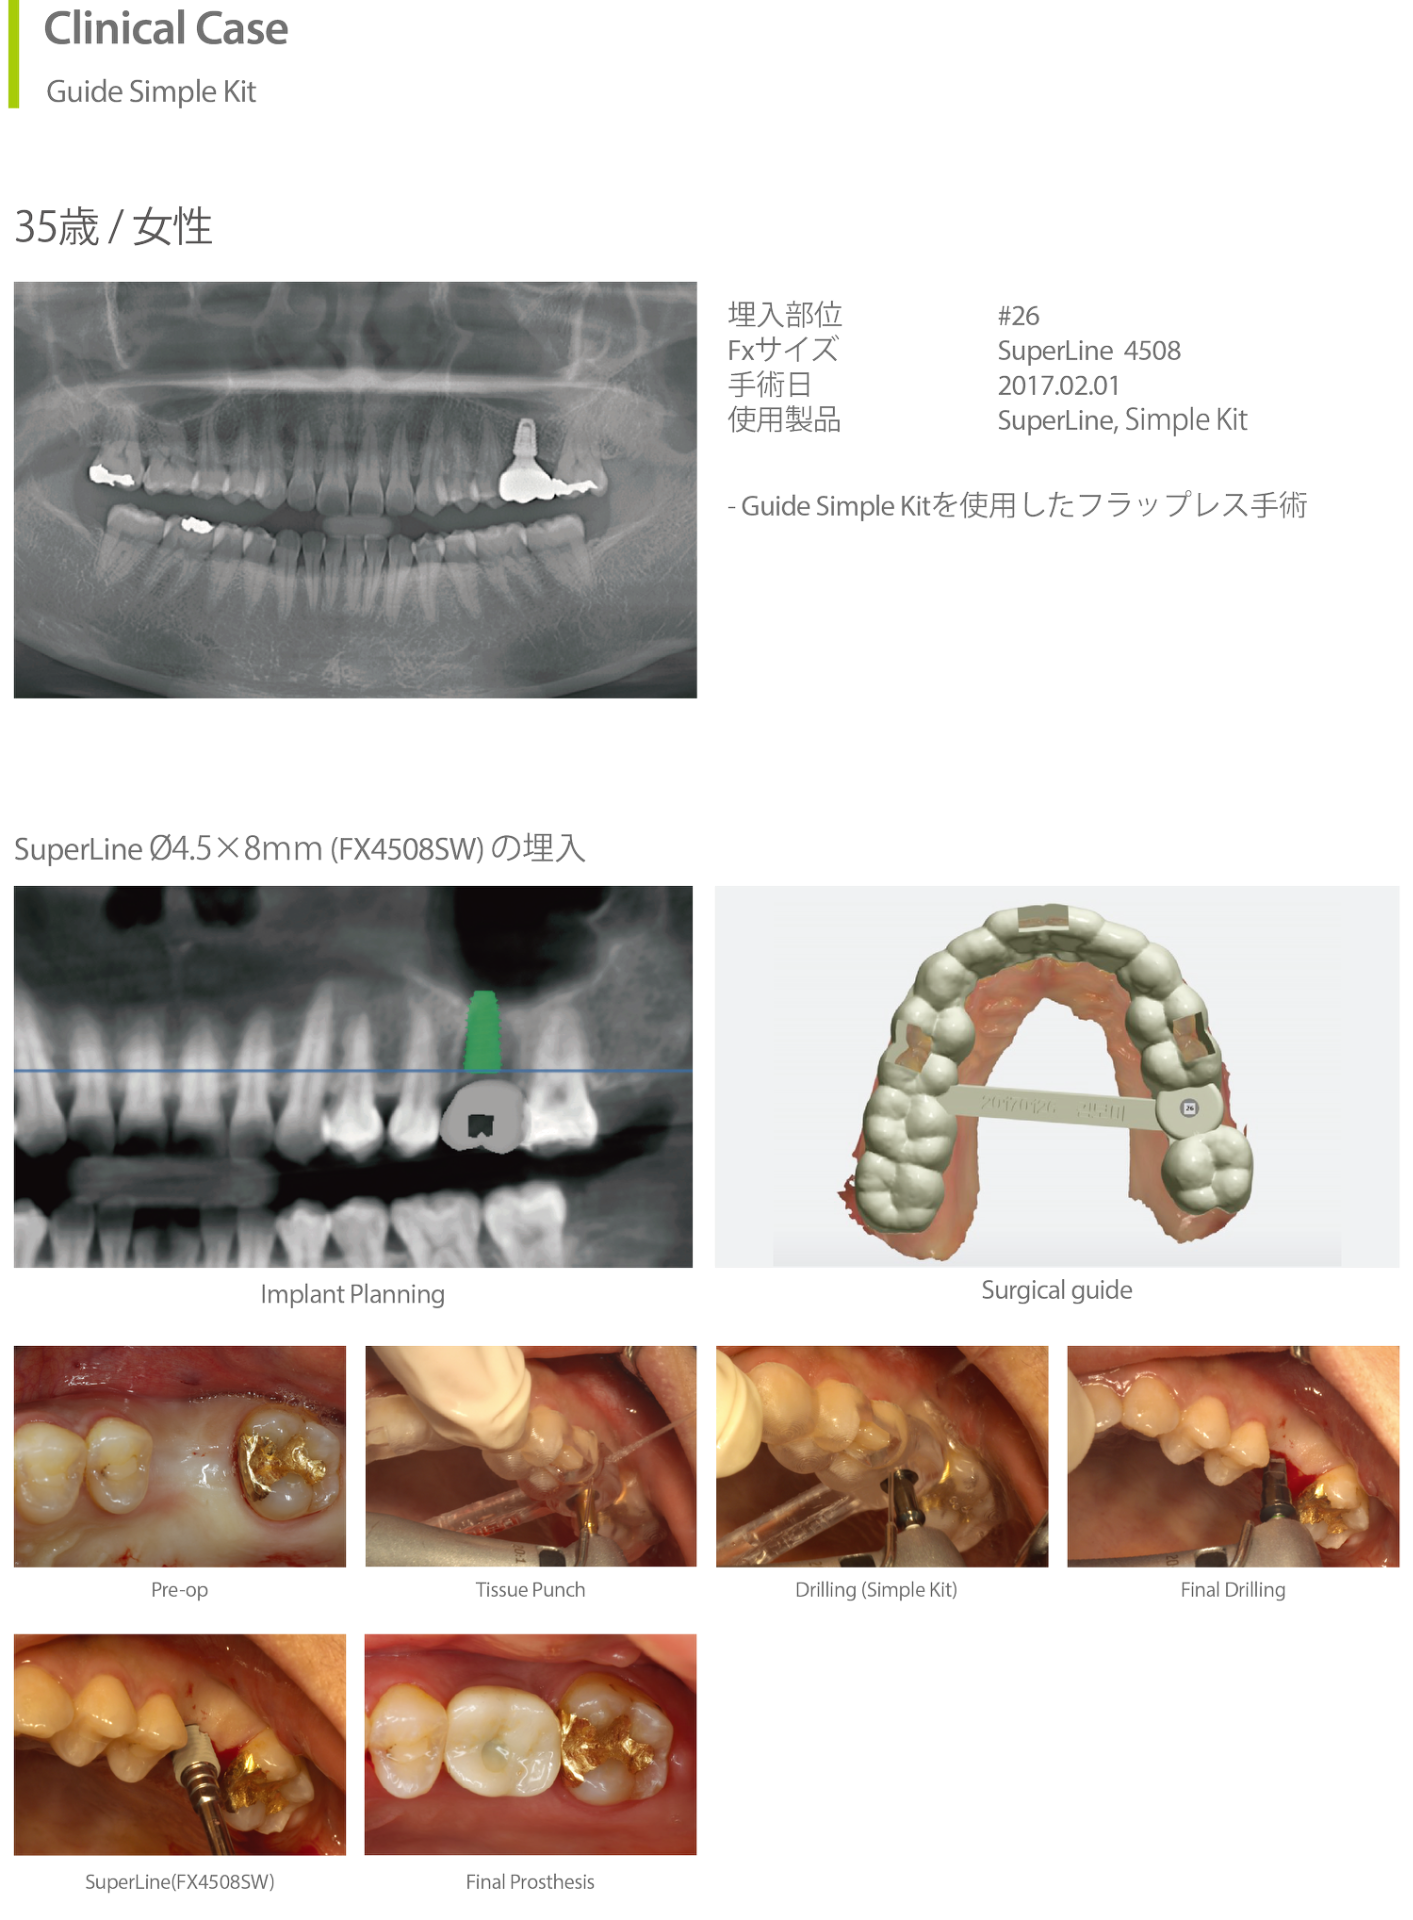

Clinical Case